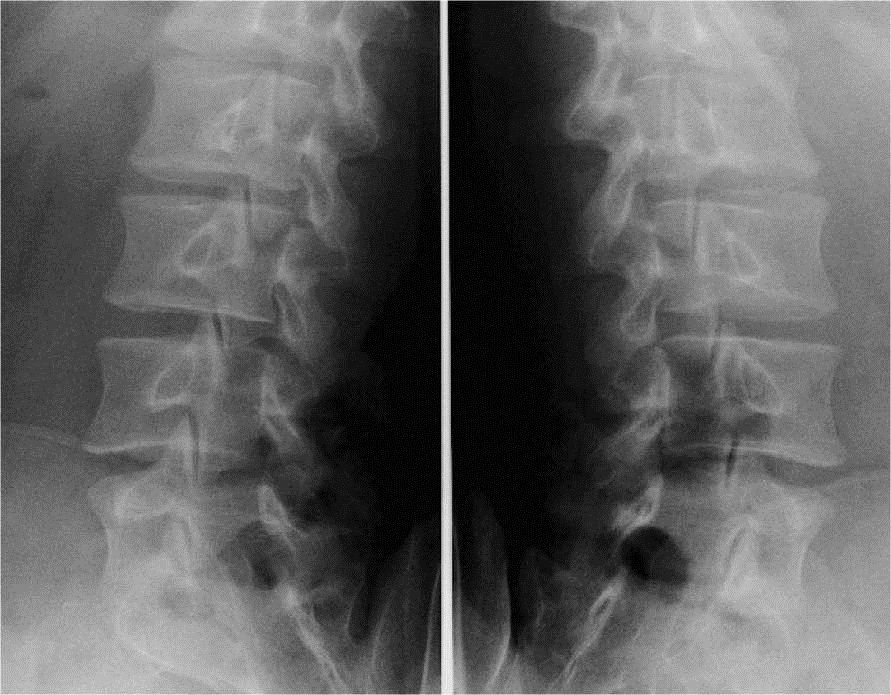

OBLIQUE OU }

C’est une incidence bilatérale

– – Le patient est debout

– – Il est en oblique postérieur droit puis gauche à

45°

RAYON DIRECTEUR

– – Il est centré sur L3 : 2 cm au-dessus de la crête iliaque et à la verticale du mamelon du coté surélevé

– – Il est horizontal

CRITERES DE REUSSITE

– – On doit voir les petits chiens de la chapelle

ANATOMIE RADIOLOGIQUE

IMAGE NORMALE

- – Pédicule

- – Apophyse articulaire supérieure

- – Apophyse transverse

- – Apophyse articulaire inférieure

- – Isthme

- – Lame

- – Apophyse épineuse

- – arc opposé

OPD OPG